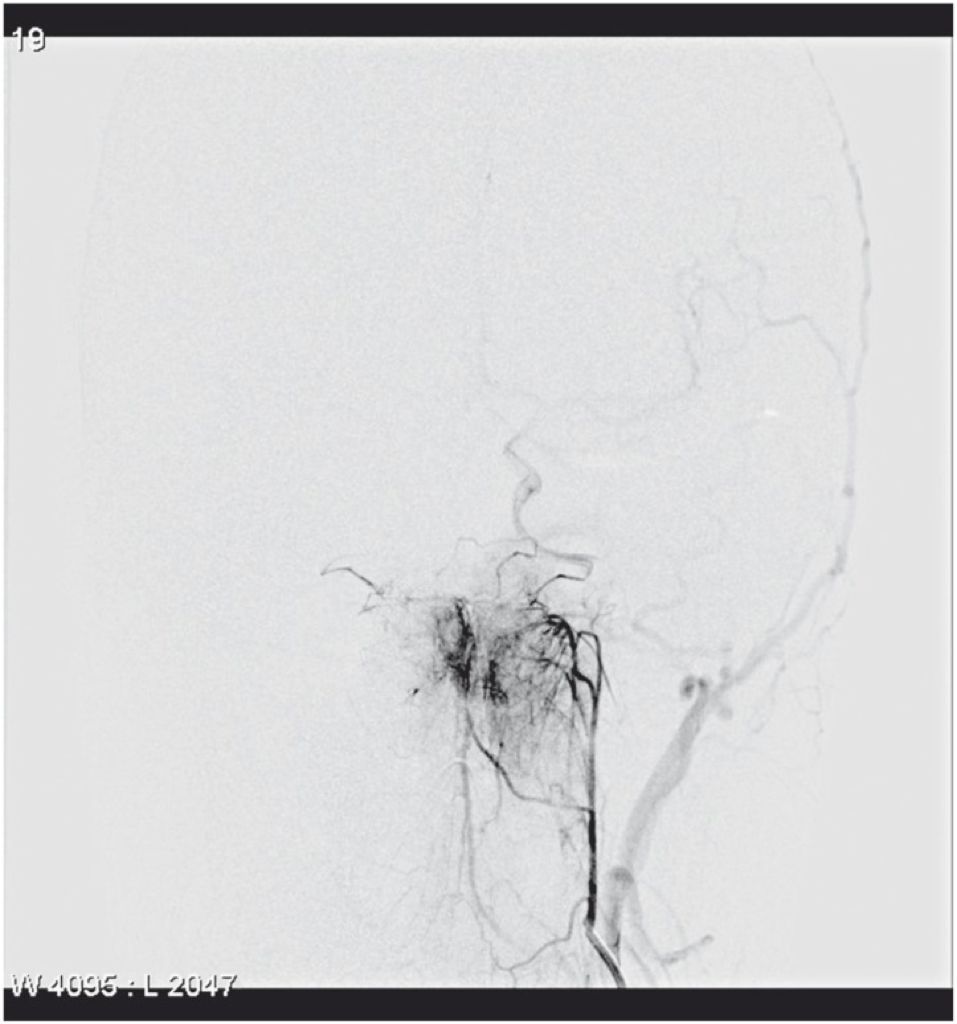

Baltsavias报道了一例(Baltsavias 2012)。选择性左侧颈内动脉造影,咽升-鼓室-镫骨动脉发自颈内动脉颈段的内侧部,向后外侧,通过中耳,走行至颅中窝底部。

![]()